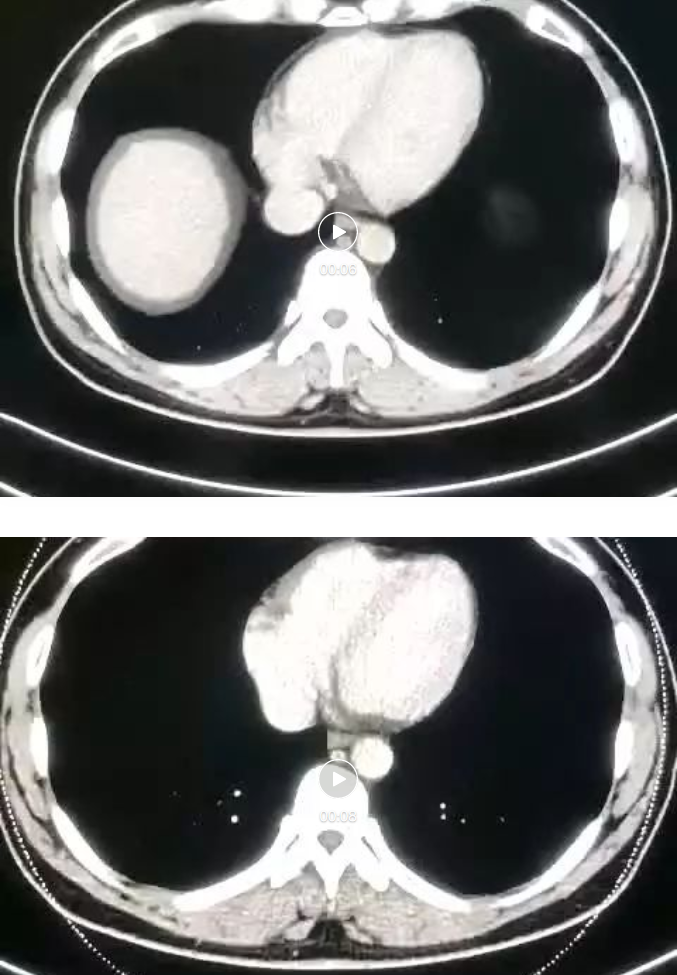

NO.2【腹部CT平扫及CT增强】

胃充盈良好,胃窦部局部胃壁环形增厚,胃腔变窄,脂肪间隙未见明确肿大淋巴结;肝脏大小、形态如常,肝实质内未见明显异常密度影;肝内外胆管无扩张;胆囊术后确如;脾脏体积无增大,亦未见明显异常密度影。胰腺形态可,未见异常密度影。双侧肾脏大小、形态如常,实质内未见明显异常密度影,双侧肾盂内见少量液性密度影。双侧输尿管走行区未见明显结石及软组织密度影。膀胱充盈良好,壁光整,腔内未见明显异常密度影。腹膜后未见明显肿大淋巴结。

胃窦部局部胃壁环形增厚,多考虑胃窦癌,请结合胃镜检查